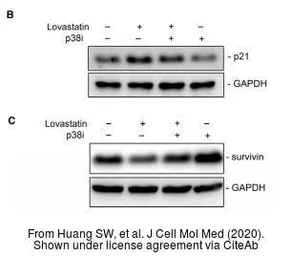

The data was published in the journal J Cell Mol Med in 2020. PMID: 31821701